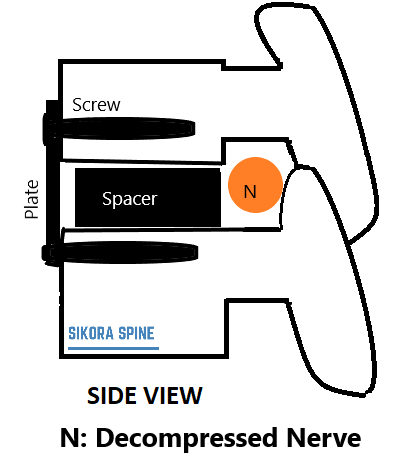

Drawing of Implant in Neck Showing Relief of Nerves

An ACDF is a fusion procedure where damaged herniated disc and arthritic bone is removed and substituted with a spacer. This is meant to remove the pressure off the nerve and spinal cord and combining the vertebrae from above and below.

The spacer is placed. This is repeated at multiple levels as needed. Sometimes a plate is placed on the front of the bone to stabilize.Intraoperative X-rays are done to confirm placement, and the wound is checked for bleeding and the incision is sutured closed.